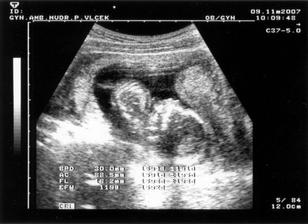

Náš svatební den byl 7.7.2007 a mimísek na sebe nenechal dlouho čekat 🙂 Už 21.8.2007 jsme na testu objevili // a těhu průkazku jsme dostali 12.10.2007. Naše bublinka by se měla narodit na konci dubna, tak uvidíme, kdy se jí bude chtít na svět.